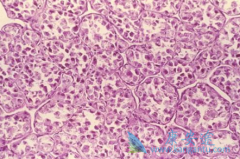

在临床上,有很多患者对 特发性肺纤维化 (IPF)和特发性肺间质纤维化(特发性间质性肺炎,IIP)傻傻分不清楚,总觉得他们是同一种病的不同叫法。而事实上,特发性肺纤维化和特发性肺间质纤维化不是一回事。那到底什么是特发性肺纤维化(IPF),什么又是特发性 ...